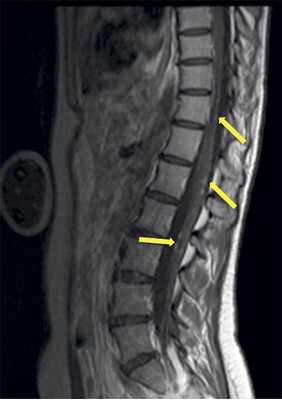

Сирингомиелический синдром при опухоли

Сирингомиелией называют образование полостей в спинном мозге, наполненных жидкостью. Они могут возникать как осложнение опухолей — примерно в 30 % случаев новообразования спинного мозга приводят к их появлению [19] .

Полости сдавливают спинной мозг, при этом сначала поражаются нервные волокна, несущие в мозг информацию о температуре и боли. Затем повреждаются волокна, передающие сигналы из мозга к мышцам. В результате пациенты становятся менее чувствительны к температуре и боли, их руки и ноги слабеют.